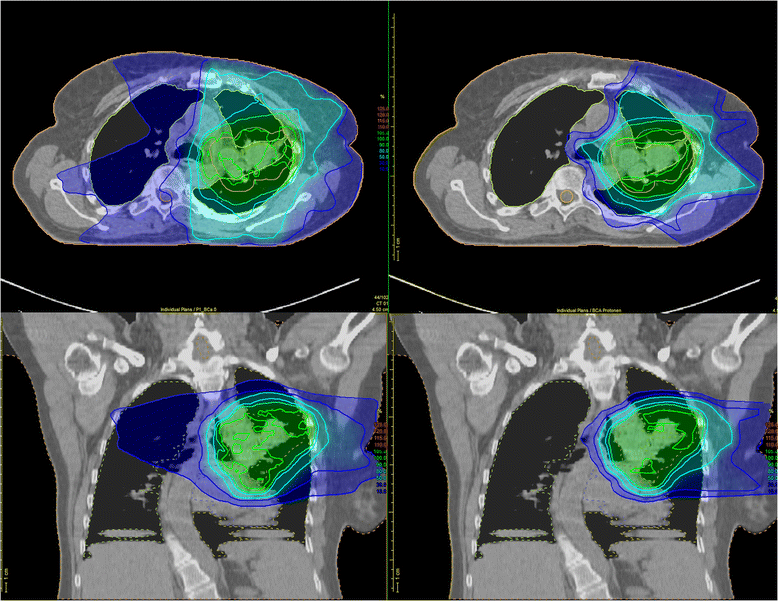

Proton beams have been used for cancer treatment for more than 28 years, and several technological advancements have been made to achieve improved clinical outcomes by delivering more accurate and conformal doses to the target cancer cells while minimizing the dose to normal tissues. That’s where proton therapy has the advantage for many lung cancer and other thoracic cancer patients. In lung cancer, proton therapy, when compared with photon treatment, has significant dosimetric advantages, with reduced dose to normal lung, esophagus, heart and other oars.

6 in a study by the university of texas md anderson cancer center of patients with inoperable nsclc, proton therapy reduced dose to normal lungs, esophagus, spinal cord. This unique feature of proton therapy: Proton therapy targets the lung tumor more precisely than other forms of radiotherapy, reducing excess radiation to the uninvolved lung, heart, and other mediastinal structures.